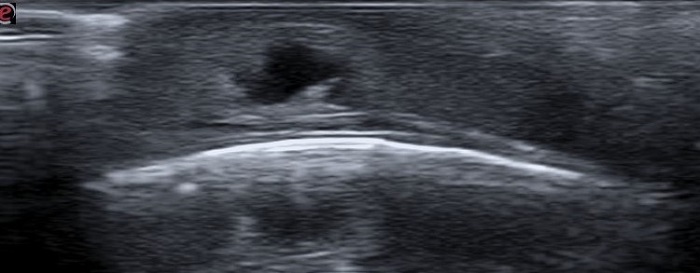

Paciente de 7 meses que acude a consulta por lesión en cuero cabelludo de crecimiento progresivo. Antecedentes personales de plagiocefalia en tratamiento con ortesis craneal. En la exploración física destaca nódulo eritematoso de 2 x 2 cm, no fluctuante y sin secreción local (Figura 1). Se realiza ecografía clínica de la lesión, donde se visualiza imagen homogénea en tejido celular subcutáneo, con leve captación Doppler y en su interior un área irregular anecoica, compatible con absceso (Figura 2). Se realiza drenaje de la lesión con salida de abundante componente purulento. Se pauta tratamiento con antibioterapia tópica y oral durante 7 días. Buena evolución clínica posterior, sin reaparición de nuevas lesiones, pero con mínima lesión cicatricial residual.

| Figura 2. Ecografía clínica de absceso en calota. Se visualiza imagen homogénea en tejido celular subcutáneo, por encima de calota y sin modificarla; en su interior, área irregular anecoica, compatible con absceso |